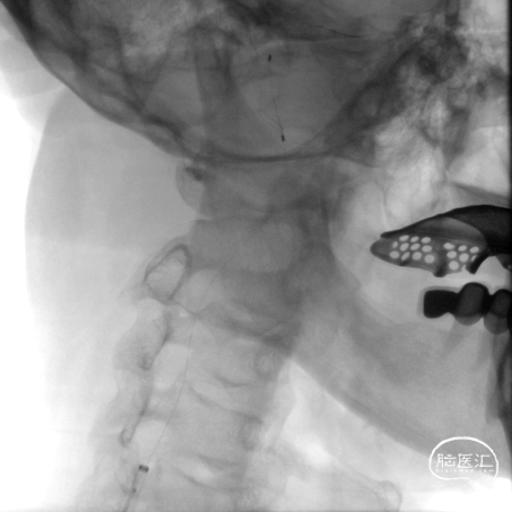

泥鳅导丝、125cm MPA1导管及088*90cm MidAccess™导引导管同轴超选右侧颈总动脉。

植入8*30mm Protege支架,回收PathGuard®保护伞。